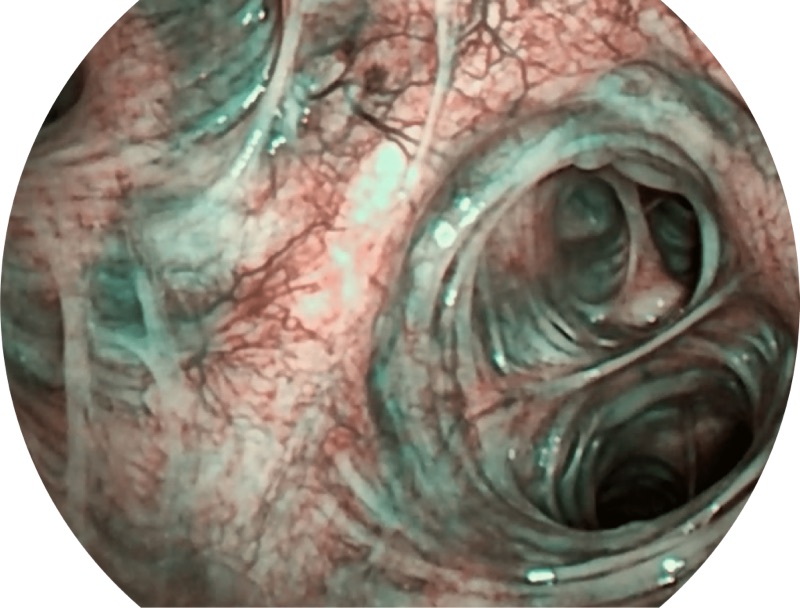

VIST